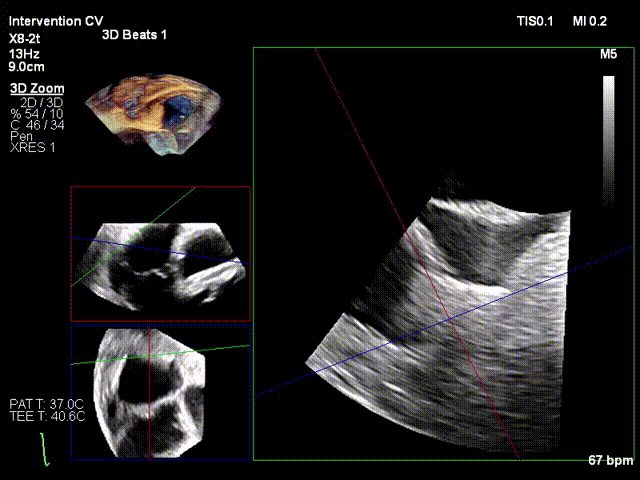

Ultrasound Evaluation: Severe tricuspid insufficiency (mean vena contracta 9mm), with the regurgitation orifice located at the anteroseptal commissure. The mechanism of regurgitation is myxomatous degeneration of the valve leaflets, accompanied by poor leaflet coaptation or reduced coaptation height. The mean diameter of the tricuspid annulus is 37mm. Echocardiographic evaluation confirmed that the anatomical structure is suitable for the K-Clip® system.

After the patient was placed under general anesthesia, the jugular vein was punctured intraoperatively to establish surgical access. An 18Fr delivery sheath was advanced along a stiff guidewire to the mid-inferior right atrium, and the delivery system was introduced under ultrasound guidance. A 12T K-Clip® device was implanted at the posterior annulus, and another 12T K-Clip® device at the anteroposterior annulus respectively. The angle between the device and the annulus plane was adjusted through catheter deflection and rotation, directing the tip of the clip device to the target position. The anchoring component was deployed into the annulus under ultrasound MPR mode; after confirming stable traction, the clamping arms were opened and apposed to the annulus, followed by retraction of the anchoring component to close the clamping arms for annuloplasty. The surgical effect was evaluated as satisfactory, and the clip components were then released.

Deployment of the anchoring component under the MPR view